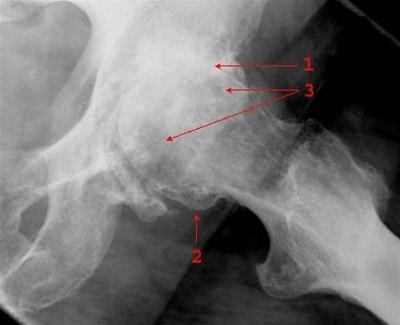

Innskutt sidebilde som viser uttalt artrose i venstre hofte med nesten utslettet leddbrusk og leddspalte (1), påleiringer (2) og subkondral sklerose og cystiske oppklaringer (3)